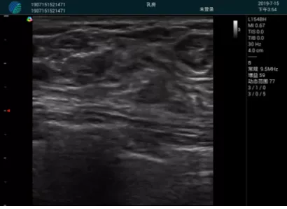

清晰顯示腺體內(nèi)低回聲快影,邊界清晰,包膜較光滑

確定進(jìn)針路徑并實(shí)時(shí)監(jiān)測(cè)抽吸針與腫塊位置關(guān)系

抽吸針進(jìn)入腫塊內(nèi)部進(jìn)行旋切

抽吸過程中可見腫塊明顯縮小,并根據(jù)腫塊位置改變針道位置

抽吸旋切后再進(jìn)行超聲復(fù)查,原腫塊區(qū)域未見殘留組織及出血